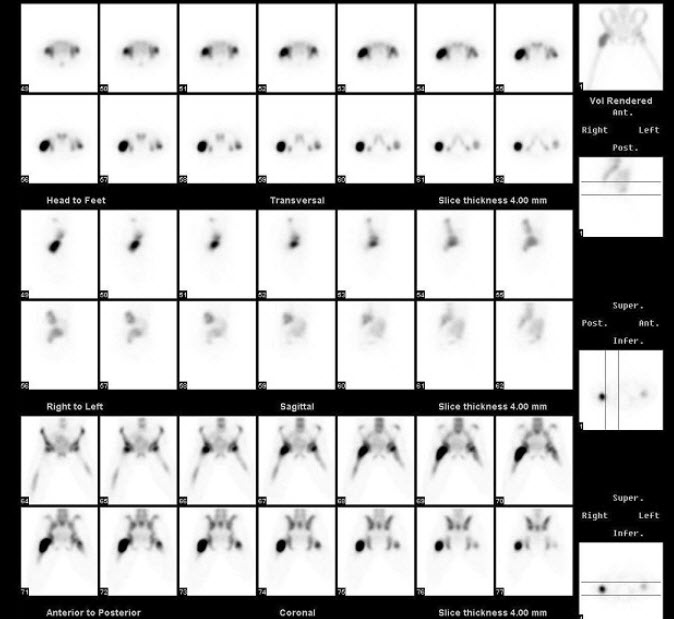

13、多项选择题

一男性病人的99Tcm-MIBI运动-静息心肌灌注显像如图,可能的诊断是()

A.左心室无心肌缺血

B.左心室前壁缺血

C.左心室心尖缺血

D.左心室前侧壁缺血

E.左心室后壁缺血